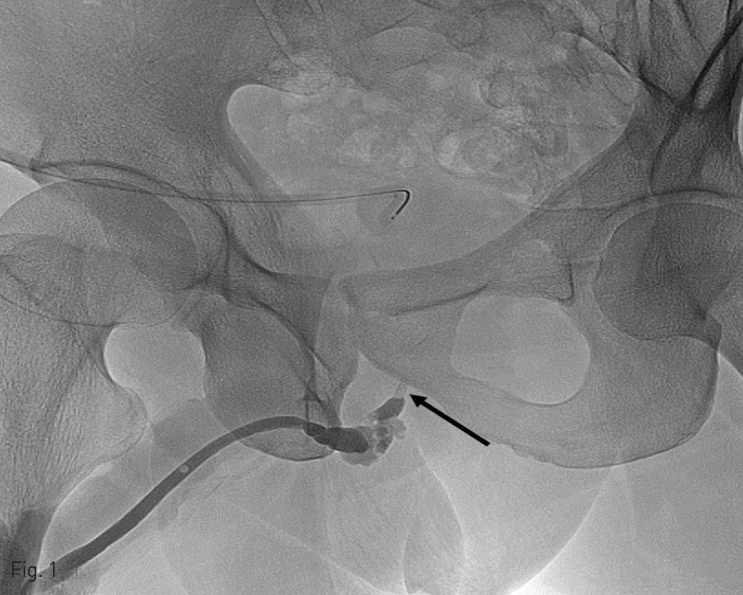

Fig. 2

A. With support from the 5-Fcatheter, a guide wire is passed into the tip of the 'beak' under fluoroscopic guidance, and then reaches the entrance of the bladder neck.

5 Fr catheter (KMP, Cook, Bloomington, Indiana)을 요도 입구에 삽입한 다음, 2% lidocaine 10mL을 catheter 내로 주입하여 국소 마취를 시행 하였다. 요도 손상 부위 및 정도를 평가하기 위해 조영제를 주입하여 역행성 요로 조영술을 시행하였다. 투시 유도 하에, 0.035 인치 유도 철사 (Terumo, Tokyo, Japan)가 탑재된 catheter을 요도 입구에 삽입하고, 손상된 요도를 지나갈 때까지 이를 조정하였다. 일단 유도 철사가 손상 부위를 지나면, 유도 철사를 방광까지 넘긴 다음 이를 따라 catheter을 방광까지 넘겼다. 그리고 나서 유도 철사를 제거하고, 조영제를 catheter 내로 주입하여 catheter 끝이 방광 내에 있음을 확인한 후, 0.035인치 딱딱한 유도 철사 (Terumo, Tokyo, Japan)을 catheter내로 삽입하여 이 유도 철사를 방광내에 말아 놓았다. Catheter을 제거한 다음, 0.035인치 딱딱한 유도 철사를 따라 14 Fr 요도관을 삽입하는데 성공 하였다.